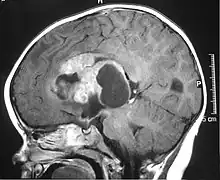

MRI of an AT/RT | |

- Magnetic resonance imaging (MRI) of the brain and spine

The initial diagnosis of a tumor is made with a radiographic study (MRI[22] or CT-). If CT was performed first, an MRI is usually performed as the images are often more detailed and may reveal previously undetected metastatic tumors in other locations of the brain. In addition, an MRI of the spine is usually performed. The AT/RT tumor often spreads to the spine. AT/RT is difficult to diagnose only from radiographic study; usually, a pathologist must perform a cytological or genetic analysis.

Appearance on radiologic exam

AT/RTs can occur at any sites within the CNS; however, about 60% are located in the posterior fossa or cerebellar area. The ASCO study showed 52% posterior fossa; 39% sPNET; 5% pineal; 2% spinal, and 2% multifocal.[3]

The tumors' appearance on CT and MRI are not specific, tending towards large size, calcifications, necrosis (tissue death), and hemorrhage (bleeding). Radiological studies alone cannot identify AT/RT; a pathologist almost always has to evaluate a brain tissue sample.

The increased cellularity of the tumor may make the appearance on an uncontrasted CT to have increased attenuation. Solid parts of the tumor often enhance with contrast MRI finding on T1 and T2 weighted images are variable. Precontrast T2 weighted images may show an isosignal or slightly hypersignal. Solid components of the tumor may enhance with contrast, but not always. MRI studies appear to be more able to pick up metastatic foci in other intracranial locations, as well as intraspinal locations.